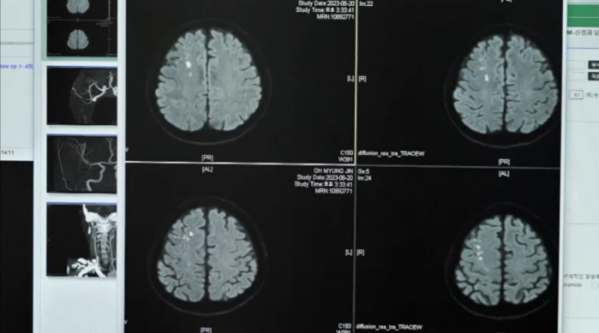

지난 5월, 왼쪽 시야에 이상을 느끼고 안과를 방문한 56세 남성 환자. 환자는 전날 퇴근길 운전 중, 내비게이션 화면이 깨져 보이는 증상이 있었다. 그러나 검사 결과, 원인은 뇌졸중으로 밝혀졌다. 우측 뇌 후두엽에 뇌출혈이 생겨, 좌측 시각 정보에 문제가 생긴 것. 건설업에 종사하는 환자는 평소 바쁘게 사는라 건강을 제대로 챙기지 못하고 있었다.

밭일을 하던 중 갑자기 쓰러져 응급실을 찾은 한 60대 남성 환자. 갑자기 왼쪽 다리와 손에 마비가 왔었다는 환자는 급성 뇌경색 판정을 받았다. 원인은 혈전(피떡)이 뇌혈관을 막아 발생하는 경동맥 협착증. 심장에서 뇌로 피를 공급하는 역할을 하는 경동맥에 협착이 일어날 경우, 뇌경색이 발병한다. 뇌경색 발병의 가장 큰 원인은 동맥경화성 뇌경색이다. 한국인에게 가장 잘 생기는 뇌경색으로 주로 뇌에 혈액을 공급하는 경동맥과 척추동맥, 중간 대뇌동맥 등 큰 동맥에 혈관벽이 두꺼워지고 탄력을 잃게 되는 동맥경화증이 생겨 발병한다. 동맥경화가 생긴 혈관은 좁아져있어 혈류의 흐름에 많은 방해를 받고, 여기에 혈전도 잘 생기게 되는 것이다.